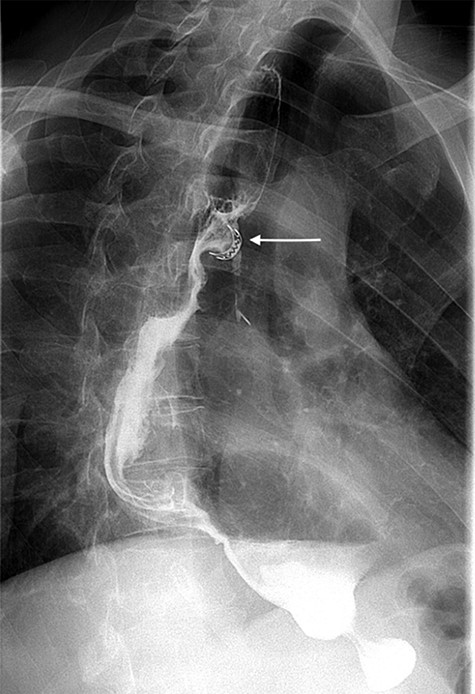

A 49-year-old male, with past medical history of tobacco smoking, who was diagnosed with adenocarcinoma of gastroesophageal junction underwent minimally invasive two-stage oesophagectomy. A month following discharge, he presented with complains of chest pain and persistent coughing (Ohno’s sign); barium swallow examination was conducted. This demonstrated a gastrobronchial fistula, between the newly formed gastric conduit and the left main bronchus (Figures 1 and 2). On endoscopic evaluation, a 5 mm communication between the tip of the gastric conduit and the left main bronchus with no evidence of ischemia and well-vascularised edges was noted.

Barium swallow demonstrating the gastric conduit (white arrow) and left bronchial tree (black arrow).